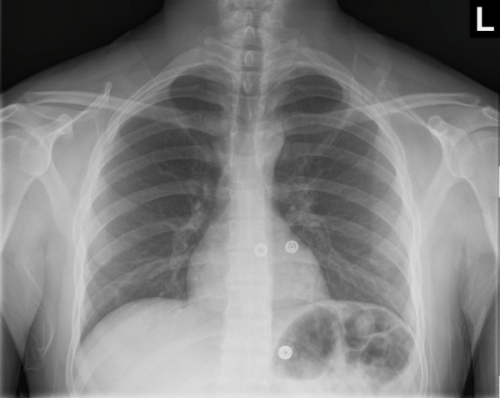

Tool to train medical student's eyes as to what a normal chest x-ray looks like, with over 500 consecutive normal images.